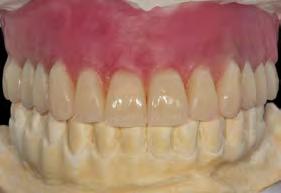

parte de los casos fueron de tipo óseo III (93.8%). El torque de inserción de los implantes varió entre 5 y 60 Ncm, siendo la media para los implantes incluidos en el estudio 34.17 Ncm (+/-18,71). Todas las prótesis se realizaron atornilladas mediante transepitelial múltiple (Multi-im®), ferulizándose los implantes entre ellos para lograr una rehabilitación completa. Como primer abordaje se llevó a cabo una prótesis de

Dentista y Paciente 52 Enciclopedia odontológica

carga progresiva terapéutica, elaborada en resina con barras articuladas como estructura metálica. El tiempo medio de seguimiento fue de 31.9 meses (+/- 17.73). Durante todo el tiempo de seguimiento, no se registraron complicaciones en las prótesis (no hubo aflojamiento de tornillos, fractura de cerámica o resina o fractura de las prótesis provisionales). No existieron tampoco fracasos en los implantes incluidos en el estudio, por lo que se puede cifrar la supervivencia en el 100%. La media de la pérdida ósea mesial de todos los implantes estudiados fue de 0.21 mm (+/- 0,40) y la media de la pérdida ósea distal fue de 0.18 mm (+/0,42). Cuando se realiza la medición de la media de la pérdida ósea mesial en función de la localización anatómica (maxilar-mandíbula), obtenemos una media de 0.33 mm (+/- 0,40) de pérdida ósea mesial para los implantes insertados en el maxilar superior

y de 0.22 mm (+/- 0,31) para la mandíbula. En cuanto a la media de la pérdida ósea distal para los implantes insertados en el maxilar superior, fue de 0.31 mm (+/- 0.41) y para la zona distal de 0.55 mm (+/- 0.34). Entre la media de la pérdida ósea mesial de los implantes insertados en el maxilar y la mandíbula no existieron diferencias estadísticamente significativas (p=0.38), ni tampoco entre la media de la pérdida ósea distal (p=0.56).

en hueso con técnicas de aumento previa, obteniéndose cifras menores para el grupo de los implantes extracortos (0.18 mm al año, 0.37 mm a los 3 años y 0.53 mm a los 5 años, con diferencias estadísticamente significativas (p<0,01 en los tres casos).1 En nuestra serie de casos, la pérdida ósea reportada para los pacientes tratados únicamente con

implantes de 5.5 mm de longitud fue de 0.21 mm en mesial (+/- 0.40) y de de 0.18 mm (+/- 0.42) en distal, por lo que son cifras similares, teniendo en cuenta que el seguimiento del estudio es de 31.9 meses. El metaánalisis que compara la pérdida ósea crestal en implantes cortos y en implantes de longitud mayor insertados en zonas de regeneración ósea1 también observa una mayor pérdida ósea crestal para los implantes del maxilar comparados con la mandíbula, pero no pudieron identificarse diferencias estadísticamente significativas, siendo concordante también con los datos arrojados por nuestro estudio.

La evidencia de que los implantes cortos ferulizados pueden presentar una predictibilidad similar a la de los implantes de mayor longitud, con un comportamiento biomecánico